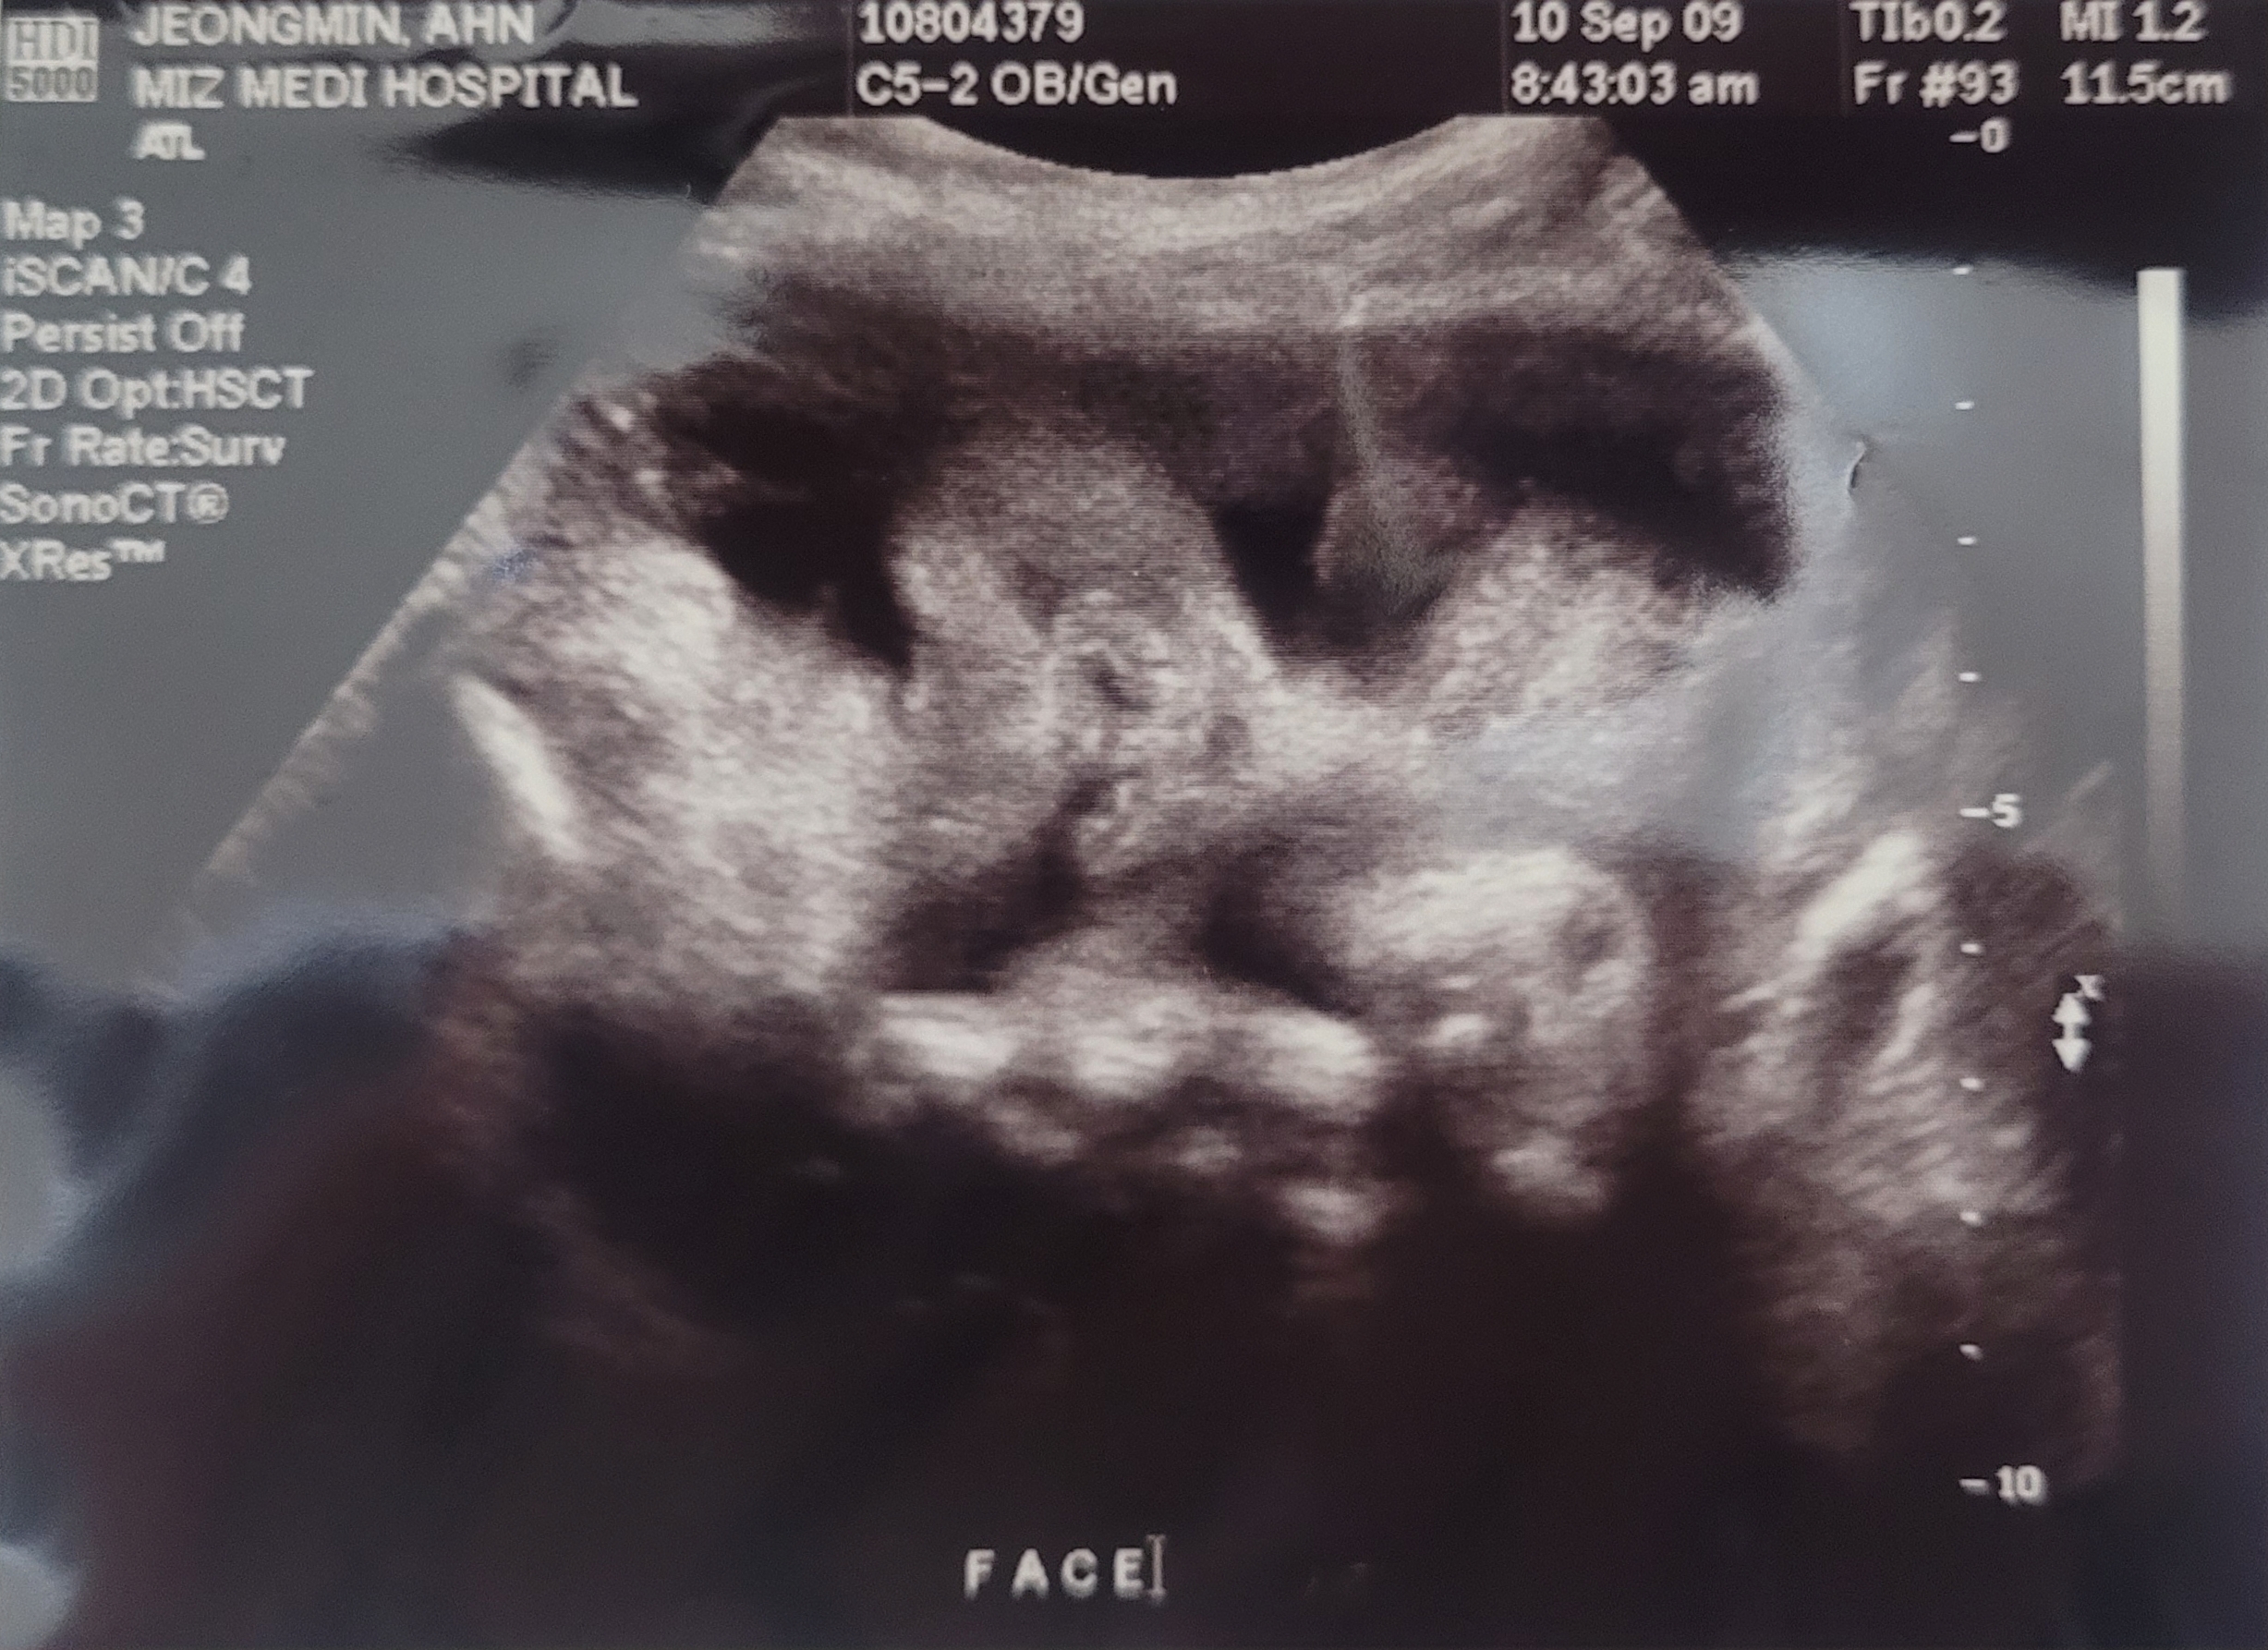

| 등기명칭 |

세상 나오기전 사랑하는 딸♡

딸의 초음파 사진

2009년 9월 10일에 찍음.

2009년 10월 6일에 태어남.

세상에 나를 만나기전 내 아이의 모습을 평생 보관할 수 있다니..

태어나기전 모습이 지금의 모습이었을까?

아들일까? 딸일까?

궁금해하며 정성을 다해 사랑하고 그 누구보다 기쁘고 행복했던 시간이었지^&^

2024년 지금은 중 3~

누구보다 무서운 사춘기 ㅠㅜ

너를 처음 키우며 감사한 일들이 많았지만 가끔 힘든 시간도 있었지..

그래도 소중하고 사랑하는 내 딸은 변함이 없는 사실이란다.

엄마한테 와줘서 고맙고, 이 세상 누구보다 널 사랑해♡♡♡